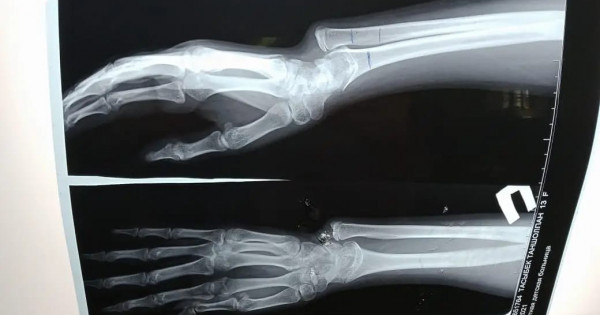

ناۋقاس وسىدان بىرنەشە جىل بۇرىن قولىن اۋىر جاراقاتتاپ, شىنتاق سۇيەگى ءوسىپ, كارى (لۋچەۆايا) سۇيەگى وسپەي قالعان. سالدارىنان قولىنداعى سۇيەكتەرى قيسايىپ, وزدىگىنەن قيمىل جاساۋعا كەدەرگى كەلتىرگەن.

«وتا جاسالعان ناۋقاس ءۇش اي بۇرىن قالالىق كلينيكالىق بالالار اۋرۋحاناسىنا كەڭەس الۋعا كەلگەن بولاتىن. تەكسەرە كەلە ناۋقاستا جاراقاتتىڭ سالدارىنان سۇيەگى قيسايعانى انىقتالدى. وپەراتسيانى بىردەن جاسامادىق. سەبەبى مۇنداي وتا بالانىڭ سۇيەك ءوسۋى توقتاۋعا جاقىنداعان كەزدە جاسالادى. وپەراتسيا كەزىندە قاتتى ءوسىپ كەتكەن سۇيەكتى قىسقارتىپ, وسپەي قالعان سۇيەككە جالعاپ, ارنايى قۇرىلعىمەن بەكىتىپ بەردىك. مۇنداي وتانى ءبىرىنشى رەت جاسادىق. وسىعان دەيىن سۇيەگى قيسىق وسكەن ناۋقاستارعا وتا جاساۋ ءۇشىن نۇر-سۇلتان قالاسىنداعى ەمدەۋ مەكەمەلەرىنە جولداما ارقىلى جىبەرەتىنبىز. ەندى مىنە مۇنداي وتانى ءوزىمىز جاساۋعا دايىنبىز» دەيدى ورتوپەد-تراۆماتولوگ باعجان تۇردىقۇلوۆ.